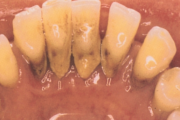

Krooniline parodontiit

Krooniline parodontiit on mikroobide poolt põhjustatud hammaste tugikudede põletik, mille tulemusena tekib progresseeruv alveolaarluu (nähtav röntgenograamil) ja periodontaalligamendi destruktsioon, igemetaskute moodustumine, igeme retsessioon või mõlemad kahjustused kombineeritult. Loe edasi »

- puudulik suuhügieen (5)

- igemepealne hambakivi (5)

- igemealune hambakivi (4)

- halb hingeõhk / suu haiseb (12)

- halb maitse suus (12)